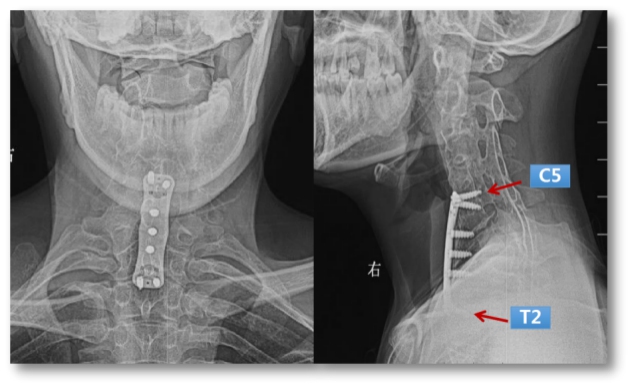

Preoperative X-ray: post-surgery ACCF, cervical multi vertebral fusion and kyphosis deformity

Preoperative CT: the left anterior bone defect of cervicothoracic vertebrae, partial screw’s original nail plate system was cut out before the spinal canal was entered.